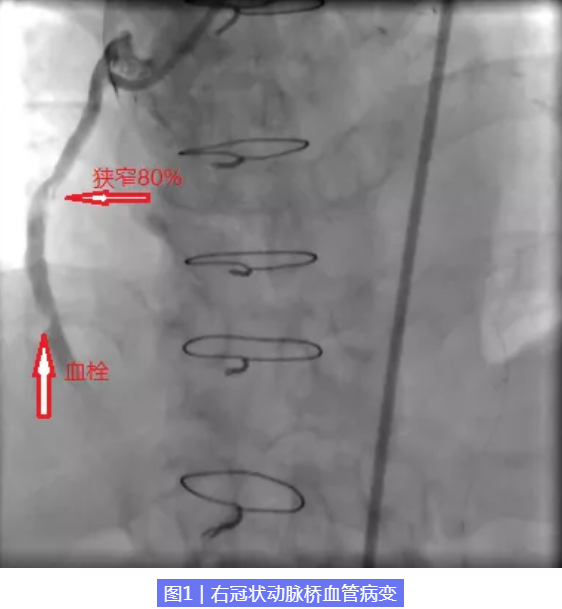

家住燕山的马大叔,今年74岁,既往有高血压、高脂血症病史,7年前,确诊为“急性下壁、右室心肌梗死”,择期行冠脉造影检查发现前降支90%狭窄,回旋支90%,右冠状动脉100%闭塞,行冠脉搭桥治疗。但近1月来反复出现胸痛,不能耐受日常体力活动,我们再次为其行冠脉造影发现右冠状动脉100%闭塞,右冠桥血管近端狭窄80%,可见大量血栓。也就是说,此次引起马大叔反复胸痛的主要血管是右冠状动脉桥血管,虽然7年前搭的桥还在,但是桥已经重度狭窄。那么,问题来了,是开通原血管还是开通桥血管?如何决策是一个艰难的选择。

由于冠状动脉搭桥术后静脉桥血管开口位置异常,“桥”支架难度极大,而且静脉桥的主要特点是富含脂质和血栓的易碎斑块,极易出现血栓、急性闭塞和穿孔,一旦出现无复流并发症,将危及性命。